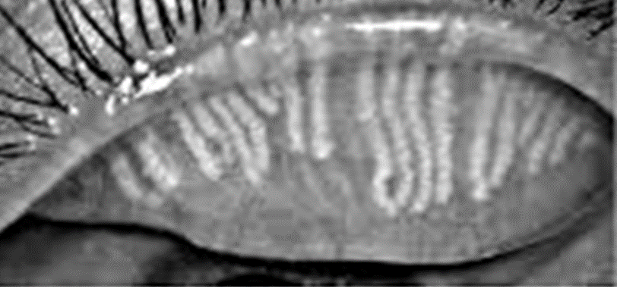

what are the signs of posterior blepharitis?

thickened meibomian secretions

microliths - plaques

meibomianitis - passive retention of secretions (chalazion, styes)

foam in tear meniscus

unstable tear film -evaporative tear deficiency

—> meibomian glands secrete oily lipid layer of tear film so reduced